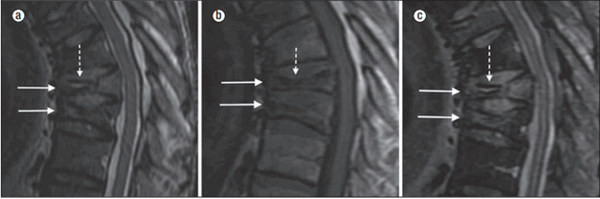

Сплошные стрелки указывают на переднюю компрессионную деформацию. На снимках а и c видна «двойная линия», то есть вакуумная расщелина (пунктирная стрелка), окруженная отеком. На изображении b визуализируется отсутствие внутри позвоночных тел вакуумных расщелин (пунктирная стрелка)[1].

Выраженная передняя компрессионная деформация тел позвонков Тh8 и Тh9 (сплошные стрелки). Внутрипозвонковые вакуумные расщелины (пунктирные стрелки) и остеонекроз[1].